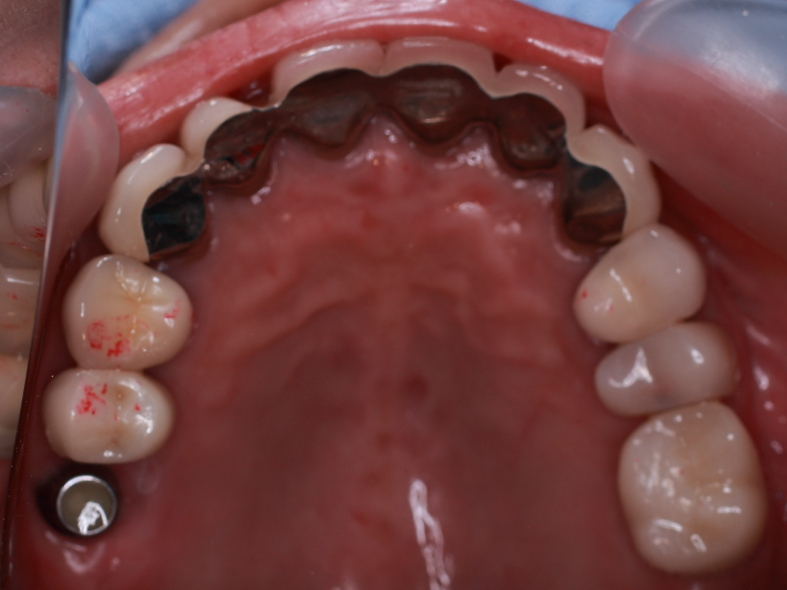

前歯の隙間を部分矯正します。

4前歯にブラケットを装着します。

3ヶ月程で隙間が無くなりました。

イメージが大分変りますネ。